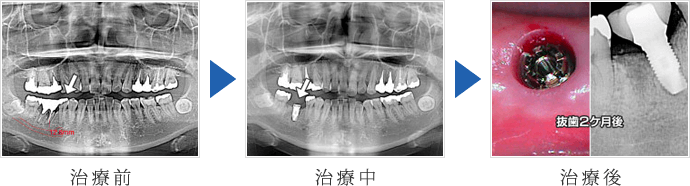

インプラント治療の症例紹介

抜歯即時インプラント症例